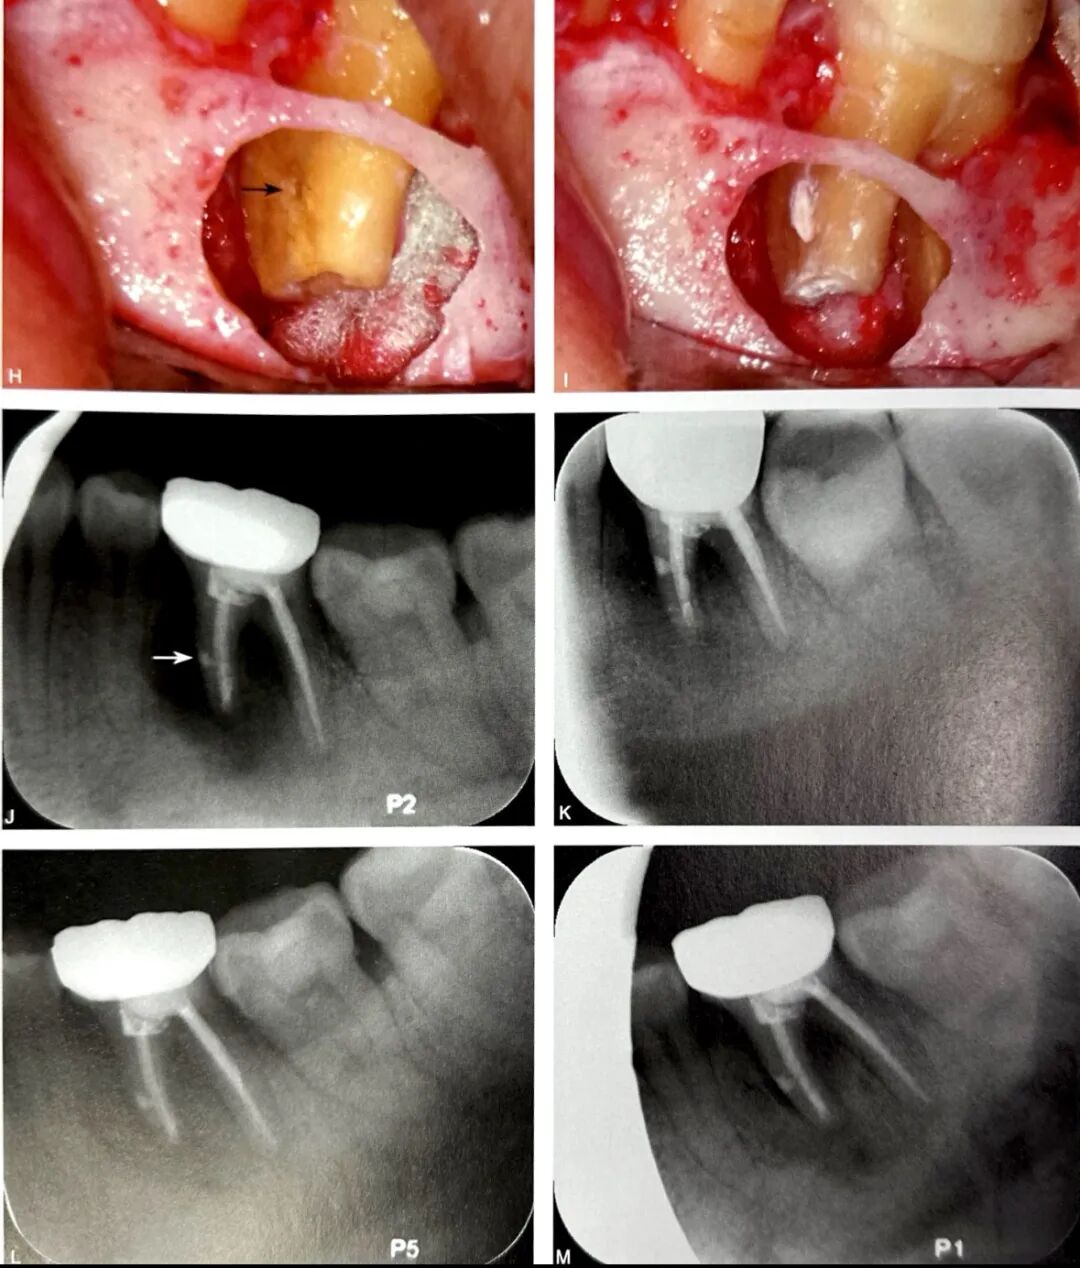

导致根旁牙槽骨破坏的可能病因有根裂、侧支根管、根折、根旁囊肿、牙骨质撕裂等。当根管侧支位于牙根中段时,感染破坏根周牙槽骨,可形成类似根裂的影像学特点,如图3所示,A为口内像颊侧面观,示左下颌第一磨牙近中近龈缘处牙龈窦道(箭头);B为根尖片示根管充填良好,近中根根尖以及根周大范围透射影,波及根分叉区;C为CBCT矢状位;D为CBCT冠状位;E为CBCT水平位,近中根根尖、根周以及根分叉区骨质破坏;F为左下颌第一牙行显微根尖外科手术,切开翻瓣牵拉 ;G为根尖周刮治和根尖切除;H为探查,近中根未见根裂线,近中面中段见根管侧支(箭头);I为主根管和根管侧支逆行预备和充填;J为术后根尖片,可见根管侧支(箭头);K为术后2个月随访根尖片;L为术后4个月随访根尖片;M为术后7个月随访根尖片;N为术后24个月随访根尖片,根周和根尖周完全愈合。